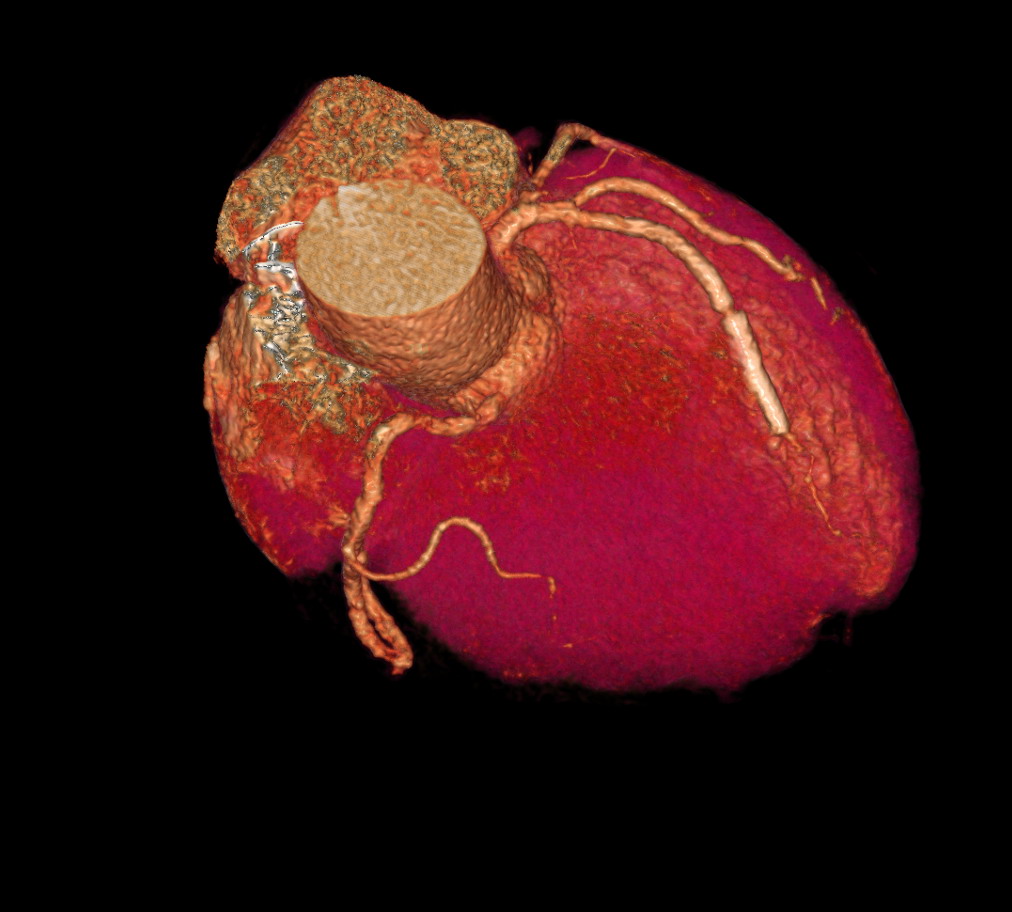

以下是引用zjzjr在2007-6-22 22:20:00的发言:[br]右冠状动脉多发狭窄,左冠状动脉支架断裂或两个支架连接欠佳。

以下是引用尚峰在2007-6-22 22:47:00的发言:[br]支架是不可能断裂的,这个病人左冠前降支病变太长,下了两个支架,但下两个支架的一个原则是两根支架必须重叠3-5mm,不知什么原因此患者两根支架没有重叠上,现在很麻烦了,要么再下一根支架,要么搭桥。